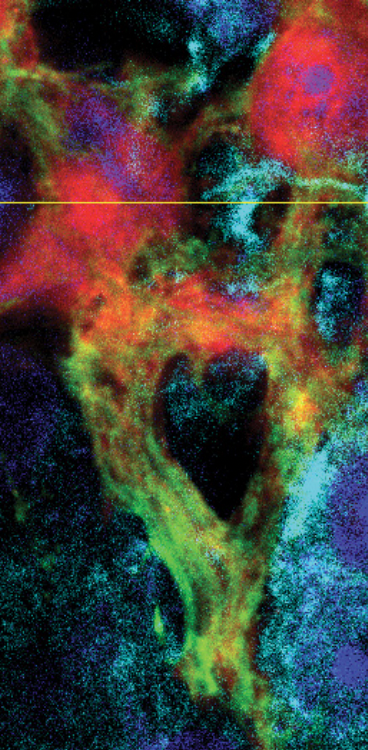

Kulkarni S et al. Age-associated changes in lineage composition of the enteric nervous system regulate gut health and disease. Elife. 2023 Dec 18.